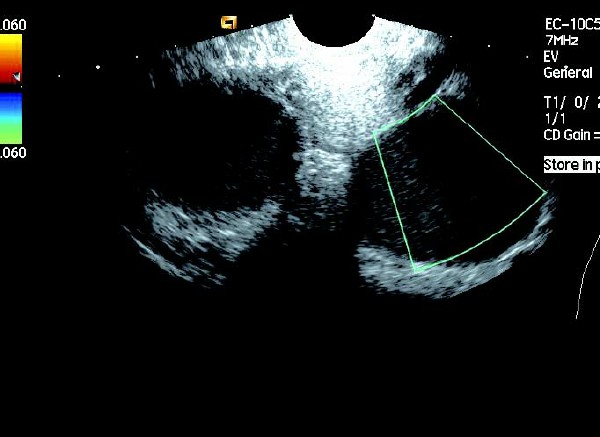

(4)CDFI 探测:囊壁及囊腔内无血流信号。

卵巢巧克力囊肿彩超描述,卵巢巧克力囊肿的超声诊断要点 2.多囊型:显现多个圆形或不规则无回声区,无回声区中有散在细小光点,其内有单个或多个光带回声,囊壁增厚,内壁欠光滑。CDFI 检测:囊壁和分隔可见条状血流信号。

患者,女,35岁。每次月经量少,痛经,近来行经期延长、疼痛加重来院诊治。超声报告显示子宫前倾位,子宫体大小为:5.9cm×5.1cm×4.8cm,形态规则,边界清晰,宫避回声匀称,宫腔线居中,内膜厚度0.6cm,宫内未见异常回声。右侧卵巢内可见大小约5.2 cm×4.9cm的无回声区暗区,壁厚,内壁欠光滑,内见密集细光点,边界清晰。CDFI探测囊壁及囊腔内无血流信号。

超声提示:右侧卵巢巧克力囊肿